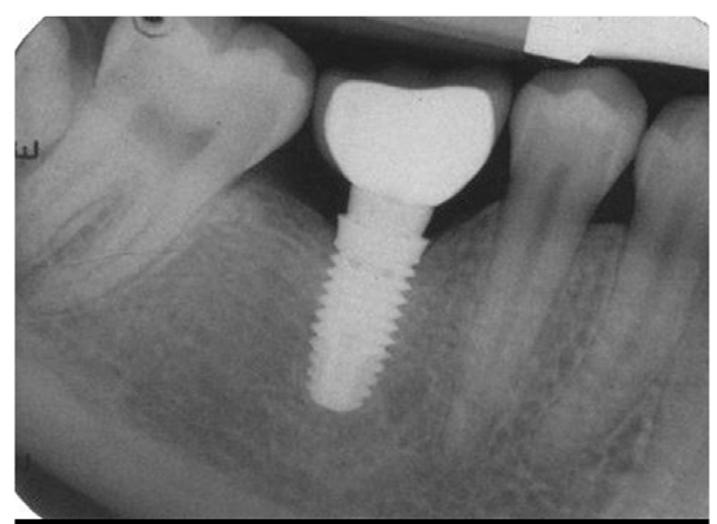

Wiele osób myśli o implancie jako o „nowym zębie”. To uproszczenie. Implant to niewielka, tytanowa śruba, która zastępuje korzeń zęba. Tytan jest materiałem biokompatybilnym, co oznacza, że organizm go nie odrzuca. Wręcz przeciwnie – zachodzi zjawisko osteointegracji, czyli trwałego zrośnięcia się metalu z kością szczęki lub żuchwy. Dzięki temu zyskujemy solidny fundament pod koronę protetyczną, która do złudzenia przypomina naturalny ząb.

Zanim dotkniemy skalpela, musimy wykonać zdjęcie pantomograficzne lub tomografię komputerową (CBCT). Na tym etapie oceniamy gęstość kości i odległość od ważnych struktur, takich jak zatoki szczękowe czy nerwy, oraz planujemy długość i grubość implantu, oraz kontakty z zębami przeciwstawnymi

To moment, w którym w znieczuleniu miejscowym umieszczamy tytanowy implant w kości. Zabieg trwa krótko i jest całkowicie bezbolesny. Po jego zakończeniu implant jest często niewidoczny w ustach, ponieważ zostaje przykryty dziąsłem na czas gojenia.

To najważniejszy etap, który trwa zazwyczaj od 3 do 6 miesięcy. W tym czasie kość dosłownie „obrasta” implant, czyniąc go integralną częścią Państwa ciała. W tym czasie pacjent może nosić uzupełnienie tymczasowe.

Gdy implant jest stabilny, odsłaniamy go i zakładamy tzw. śrubę gojącą, która kształtuje dziąsło. Po około 2 tygodniach lub skanujemy jamę ustną skanerem 3D, a technik wykonuje ostateczną koronę, którą cementujemy lub przykręcamy do implantu.